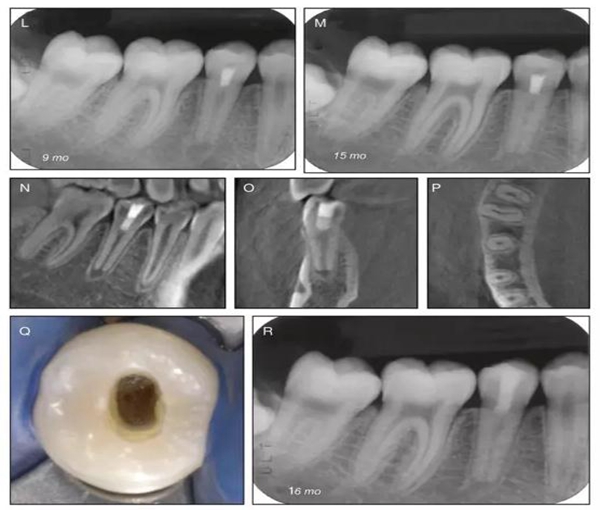

原則上年輕恒牙的牙髓治療應(yīng)盡可能以保存活髓的方式以便不影響牙根繼續(xù)發(fā)育。本文3個(gè)病例均描述了根尖尚未發(fā)育完成的下頜前磨牙被確診為牙髓壞死伴有大面積根尖病損,治療過(guò)程中在根管內(nèi)發(fā)現(xiàn)了部分活髓,而采用活髓切斷后都取得了很好的療效。